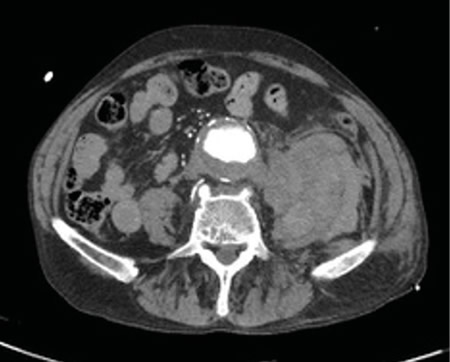

Respecto a las pruebas complementarias, en la analítica sanguínea, se halla una PCR de 39,1 mg/l, leucocitosis de 21.300/mm3, con 88 % de neutrófilos, y una hemoglobina de 10,5 g/dl. En la radiografía pélvica no se evidencian hallazgos patológicos. Debido a la hipotensión, se decide realizar un TC abdominal (Figuras 1 y 2), en el que se objetiva un aneurisma de aorta infrarrenal roto, con diámetro de 50 x 52 x 48 milímetros, a 50 mm de arteria renal derecha y a 65 mm de arteria renal izquierda, craneal a la bifurcación ilíaca. Asimismo, se aprecia un hematoma retroperitoneal en contexto de sangrado en parte posterior de la aorta, que infiltra el músculo psoas ilíaco izquierdo, justificando la clínica de coxalgia con irradiación izquierda. Se contacta con cirugía vascular, interviniéndose de forma urgente, con buena evolución posterior.

Fig. 2. TC transversal de aneurisma de aorta abdominal.